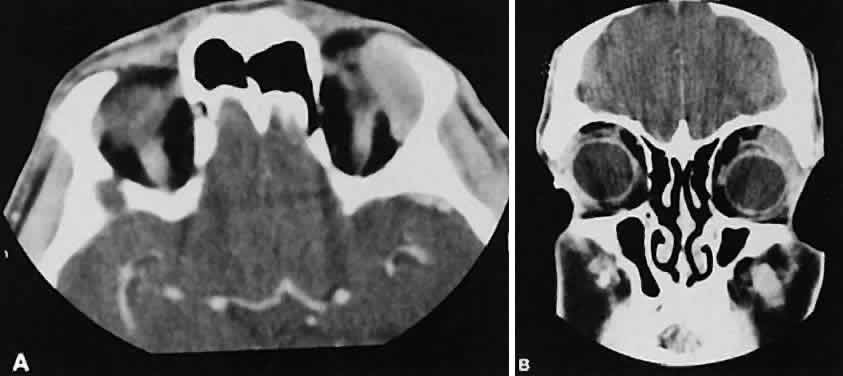

Fig. 6. Nonspecific inflammatory dacryoadenitis. An isodense enlargement of the lacrimal gland is noted on axial (A) and coronal (B) views. Note the similarity to Figure 18.

Nonspecific inflammatory dacryoadenitis shows enlargement of the lacrimal gland, which typically molds to the shape of the globe (Fig. 6). The adjacent bone is normal, and contrast enhancement of the gland usually is fairly homogeneous. Bilateral involvement may be apparent with certain conditions such as Sjogren's syndrome, sarcoidosis, lymphoma, or even Graves' orbitopathy, although enlarged EOM in the latter condition might make this a more obvious diagnosis.

Fig. 18. Axial (A) and coronal (B) views of lacrimal gland lymphoma. There is homogenous enhancement of the enlarged lacrimal gland. Compared with Fig. 6, there is no difference.

Lymphomatous involvement of the lacrimal gland resembles inflammatory dacryoadenitis radiographically. The enlarged lacrimal gland conforms to the shape of the globe, and the adjacent bone is normal (Fig. 18). We are aware of three high-grade lymphomas that affected the orbit and lacrimal gland and indented the globe, but this is distinctly unusual. Non-Hodgkin's B-cell lymphomas represent the most common type of lymphoma to affect the orbit. Literally any structure in the orbit can be subject to lymphomatous involvement; therefore, a lymphoma should be suspected in the presence of any amorphous isointense infiltrative process.